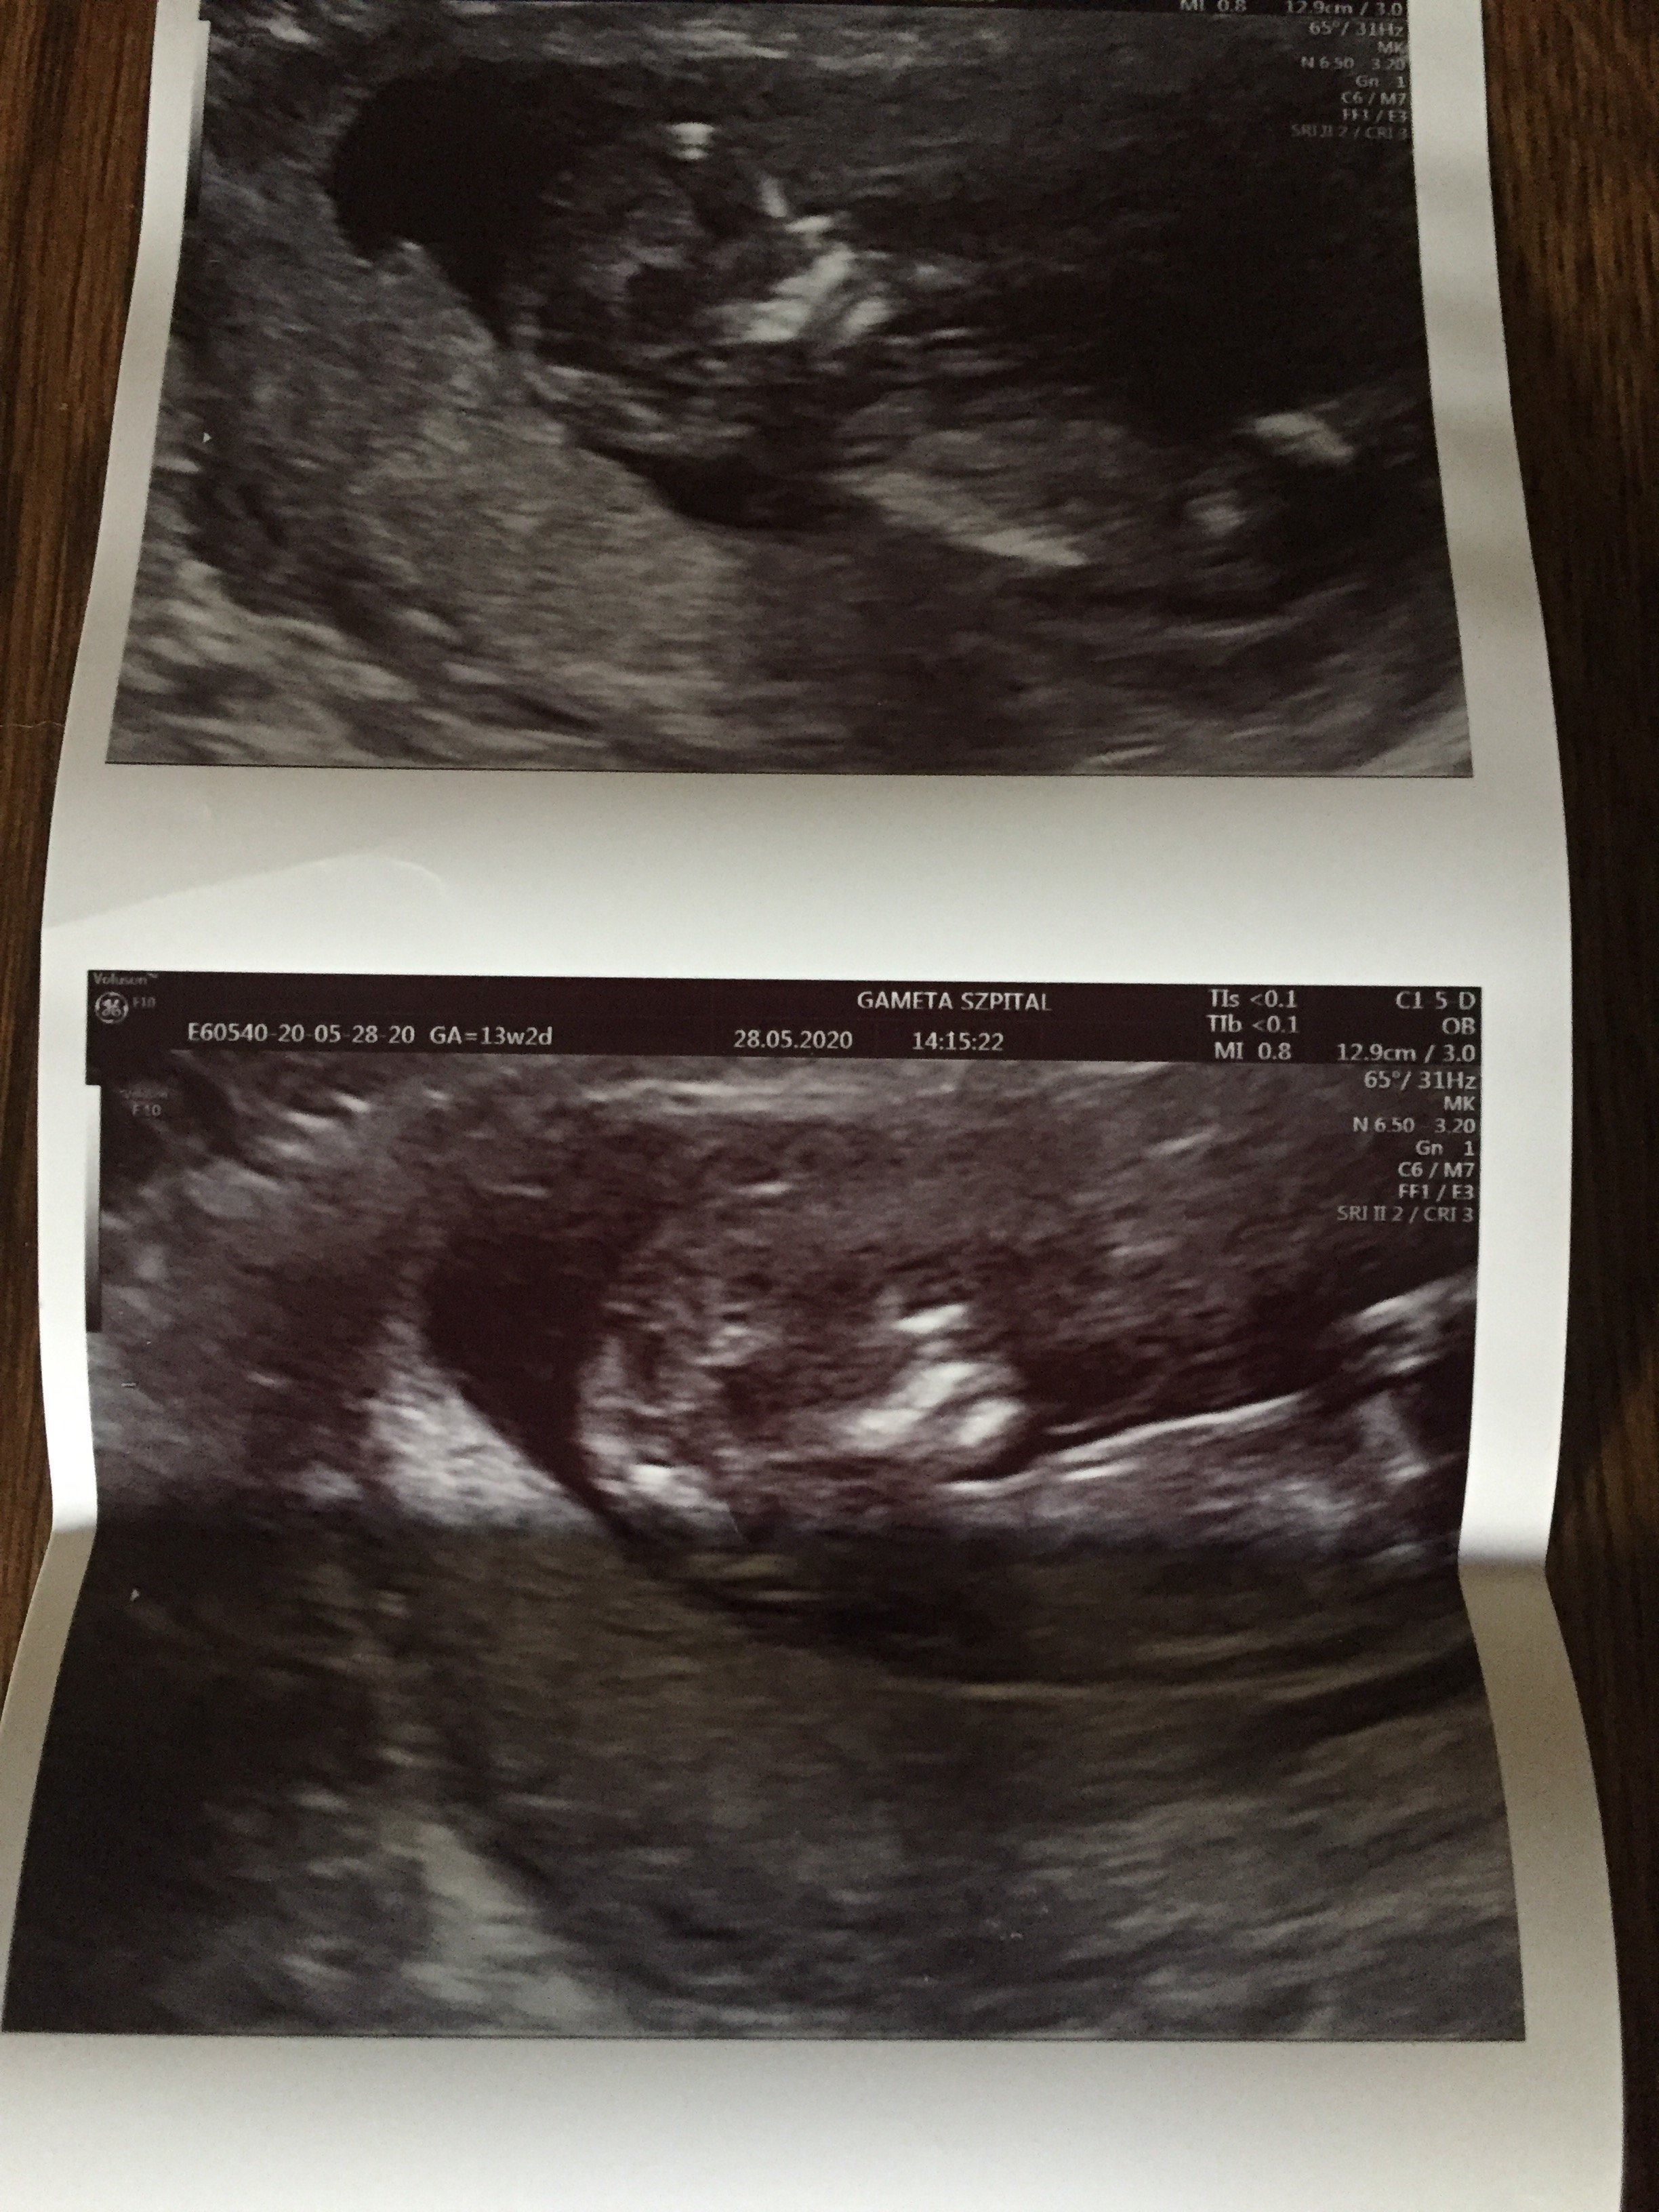

Kochana jesteś dobra w obstawianiu co u mnie widzisz ? 🤪 lekarz mówi dziewczynka a na ramxi nub różnie z przewaga na chłopaka 😂

Załączniki

• B8225E78-1DA4-41A8-AB87-C8E5F07DF65F.jpeg

B8225E78-1DA4-41A8-AB87-C8E5F07DF65F.jpeg

1 MB · Wyświetleń: 102